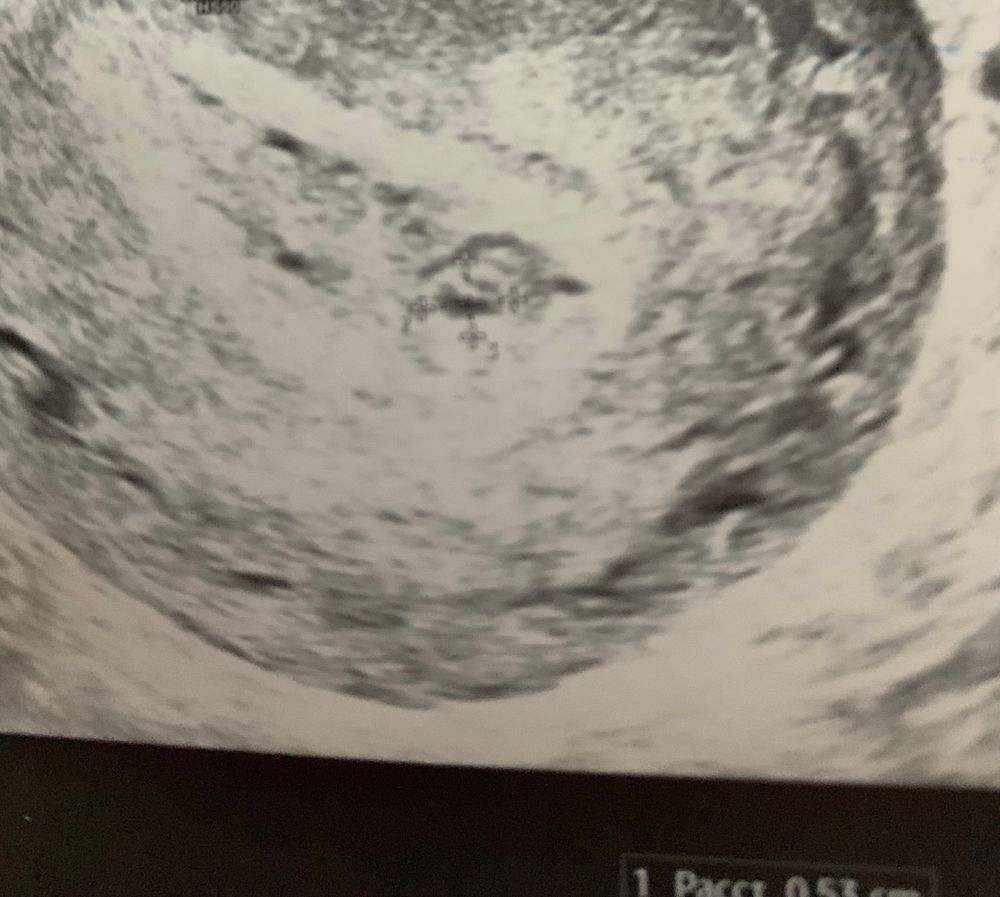

Сегодня уже в матке появилось ПЯ, пошла в другую клинику к более грамотному узисту.

ПЯ 3мм хорион 1мм (написано что соответствует 5нед, со дня зачатия так и выходит 5 недель)